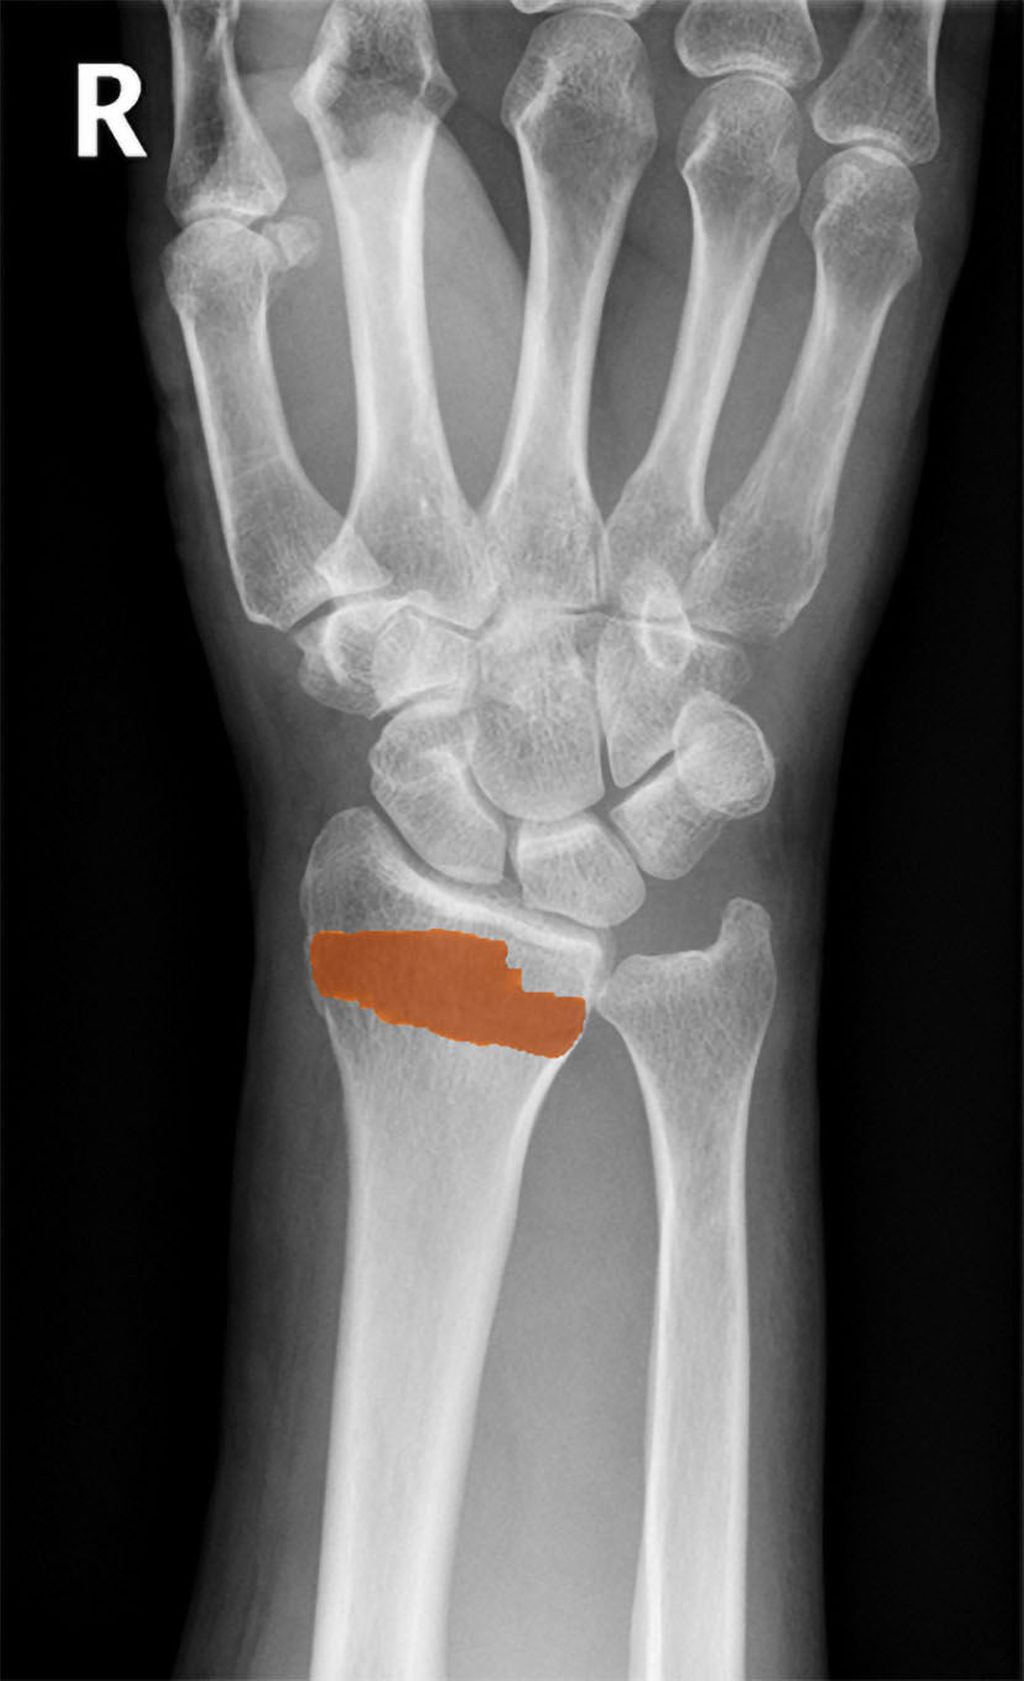

Das KI-Modell basiert auf einem Convolutional Neural Network (CNN) und wurde von Carolina Avelar, Zsolt Bertalan und Richard Ljuhar vom ImageBiopsy Lab, Wien, entwickelt und darauf trainiert, DRF in Röntgenaufnahmen zu erkennen. 85% der oben beschriebenen Röntgenbilder bildeten das Trainingsset. Ein RetinaNet mit ResNet50-Backbone identifizierte den Handgelenksbereich. Die eigentliche Klassifizierung übernahm ein modifiziertes U-Net, das für eine Doppelaufgabe optimiert wurde.Die Klassifizierung erfolgte über einen Score, der die Wahrscheinlichkeit einer Fraktur bestimmt (0 oder 1). Die Segmentierung erfolgte über eine Maske, die die Fraktur im Bild lokalisierte (Abb.1).